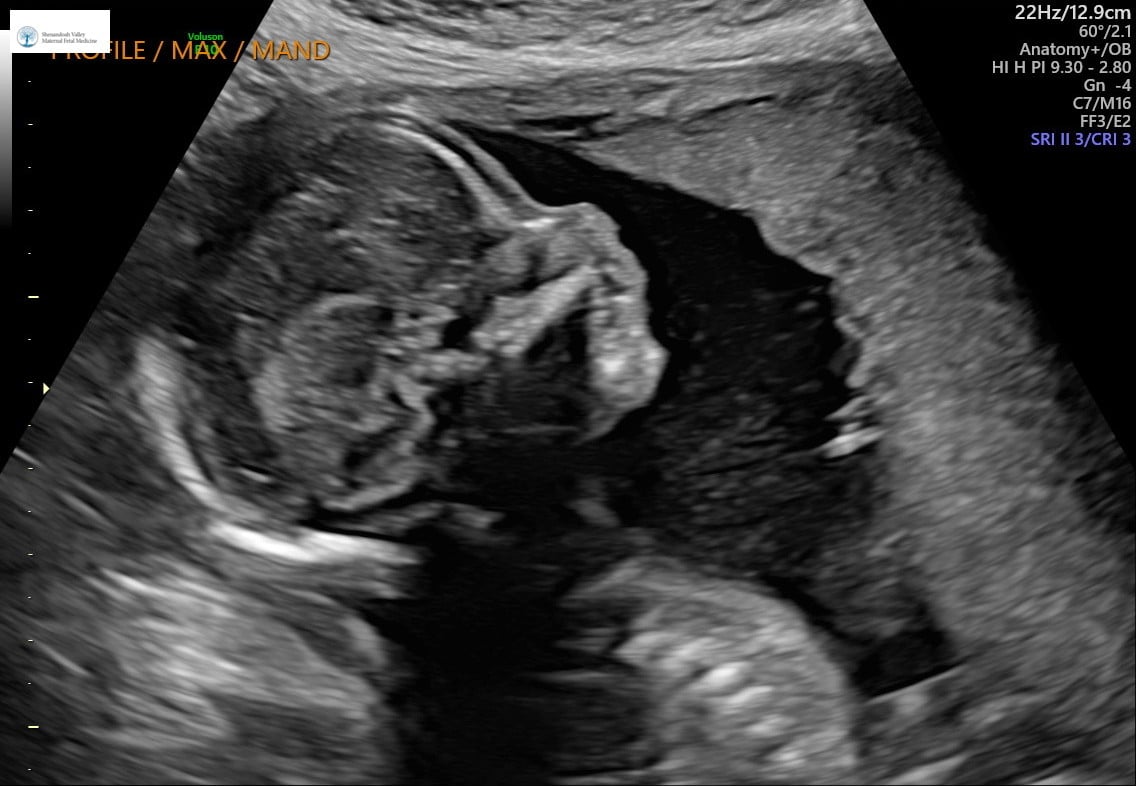

Had my anatomy scan done on Monday! They couldn’t get a good shot of baby’s face. Baby was moving around like crazy. I’ve done 5 anatomy scans before (both of my kids required me to go back for more imaging) - and I’ve never seen a baby move like this. It was wild to see! The tech was really sweet and wrote notes on the images for my kids and DH who couldn’t attend.